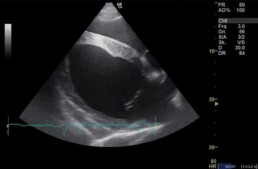

Untersuchungsbefunde (Herzultraschall)

Bei dem Wallach wurden eine klinische, elektro- und echokardiographische Untersuchung (EKG und Herzultraschall) des Herzens, sowie eine dopplerechokardiographische Untersuchung der Herzklappen durchgeführt. Auf eine elektrokardiographische Untersuchung unter Belastung wurde vorerst aufgrund der erhobenen Befunde verzichtet.

Im Rahmen der klinischen Untersuchung wurde ein Herzgeräusch und mehrere Funktionsstörungen der Herzklappen festgestellt. Der Herzmuskel des Wallachs wies ingesamt eine leichte Vergrößerung auf.

Herzultraschall